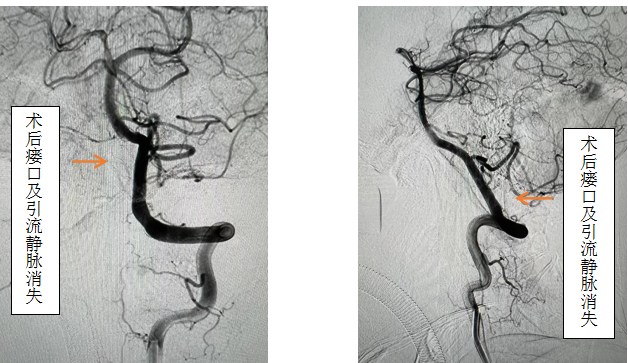

患者女性,56岁,以“双下肢无力伴感觉异常半年,加重2月”主诉入院,入院前先后辗转我省多家医院,效果欠佳。入院时已经行走困难,行颈椎核磁见颈椎蛛网膜下腔异常信号影,请神经外科会诊后考虑硬脊膜动静脉瘘可能性大,转入神外后立即由李帅主治医师行全脊髓血管造影,见“左侧椎动脉V4段发出脑膜支,其远端分支供血形成硬脊膜动静脉瘘,瘘口位于枕骨大孔区,经延髓背侧及腹侧向下引流至胸2椎体节段”。缪星宇主任主持全科病例讨论,讨论考虑患者经脊髓血管造影后诊断明确,手术指征明确,可行硬脊膜动静脉瘘介入栓塞术或开颅阻断术。术中可采取“高压锅”技术防止栓塞胶的返流,降低微导管的到位要求,降低返流空间的要求,使得返流空间安全可控,缩短注胶时间,增加胶的弥散效率,从一定程度上提高栓塞比例,增加患者的安全性。如介入微导管到位困难,可以考虑开颅阻断瘘口,但瘘口位置距离呼吸中枢延髓较近、术中风险大且术后患者恢复时间长。科室讨论后决定利用六合彩网站

先进的复合手术室,首先采用第一方案“高压锅”技术使胶完全封堵瘘口,若不能到位或完全封堵,则采用第二方案,转为开颅阻断瘘口。手术当日,由黄卫东主任医师和李帅主治医师操作,第一根栓塞微导管顺利到达瘘口,第二根微导管接近栓塞微导管后使用弹簧圈顺利形成高压锅塞子,经第一根微导管注入栓塞胶,射线透视下见栓塞胶按预期流向瘘口,栓塞满意后造影示瘘口及引流静脉均未见显影,手术成功。术后患者恢复良好,第二天即下床活动,下肢活动明显恢复,5天后步行出院。